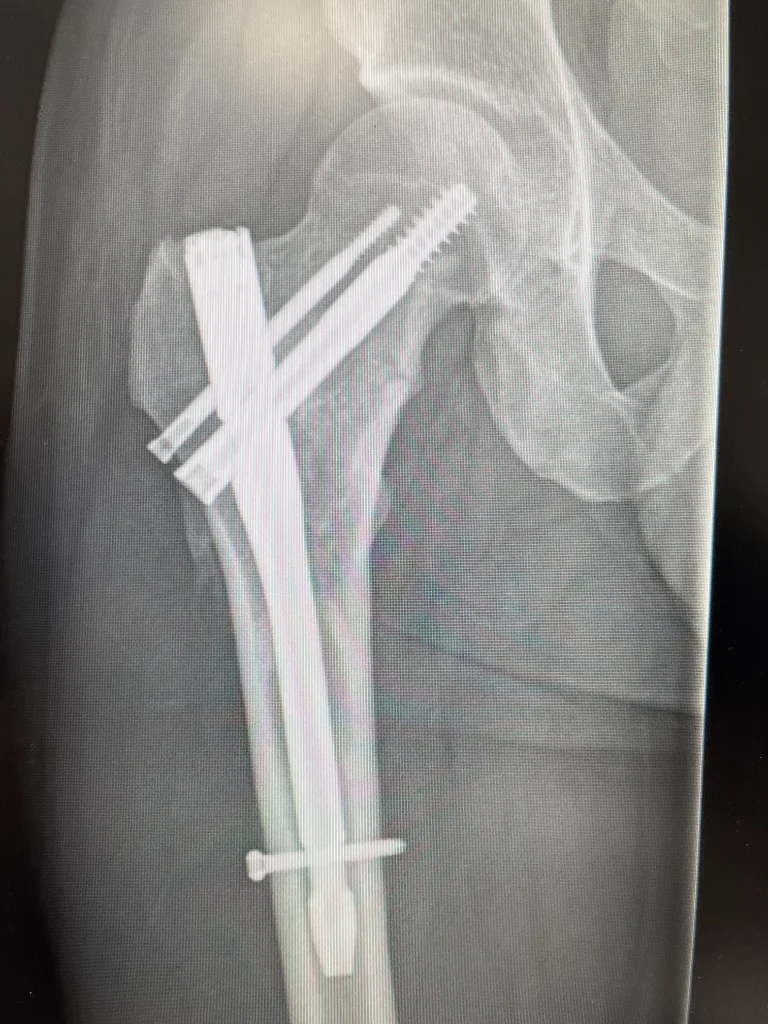

Within a week, Jordan was on an operating table having a titanium rod placed through his femur, bolted into place where his bone could no longer support him, in a procedure called intermedullary nailing surgery.

“This is to be expected when you look at an X-ray of my leg.

“It’s quickly dealt with in my mind, reminding myself of how lucky and fortunate I am to be able to be running around and making the most of my life.”